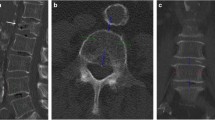

Image analysis, post-processing, and BMD calculation

On sagittal reformations, circular VOIs were manually placed in the ventral halves of L1 to L3. If one or more of these showed a pathology such as a fracture or extensive degenerative changes, adjacent thoracolumbar vertebrae were used instead. CT numbers in NE, arterial (AR), and portal-venous (PV) phases were extracted from both conventional and two virtual monoenergetic images at different energy levels (VMI; 50 and 200 keV), respectively (Fig. 1).

Sagittal (a), axial (b), and multiplanar reformation (c) of dual-layer spectral CT imaging of a 77-year-old male patient. Spinal VOIs are positioned in the ventral halves of L1–L3 (green) (VMI at 50 keV). Vascular VOIs are positioned orthogonally and mid-luminally in the abdominal aorta (red), the inferior vena cava (blue), and the portal vein (violet) (iodine density maps)

Additionally, mid-luminal iodine concentrations (mg/ml) were measured within the abdominal aorta (AA) and the inferior vena cava (IVC) on axial images—immediately inferior to the renal vessels—as well as within the vena portae (VP) on multiplanar reformations (Fig. 1). A commercially available spectral CT software was used for the generation of iodine density maps based on iodine-water decomposition (IntelliSpace Portal 10.1.0, Philips Healthcare).